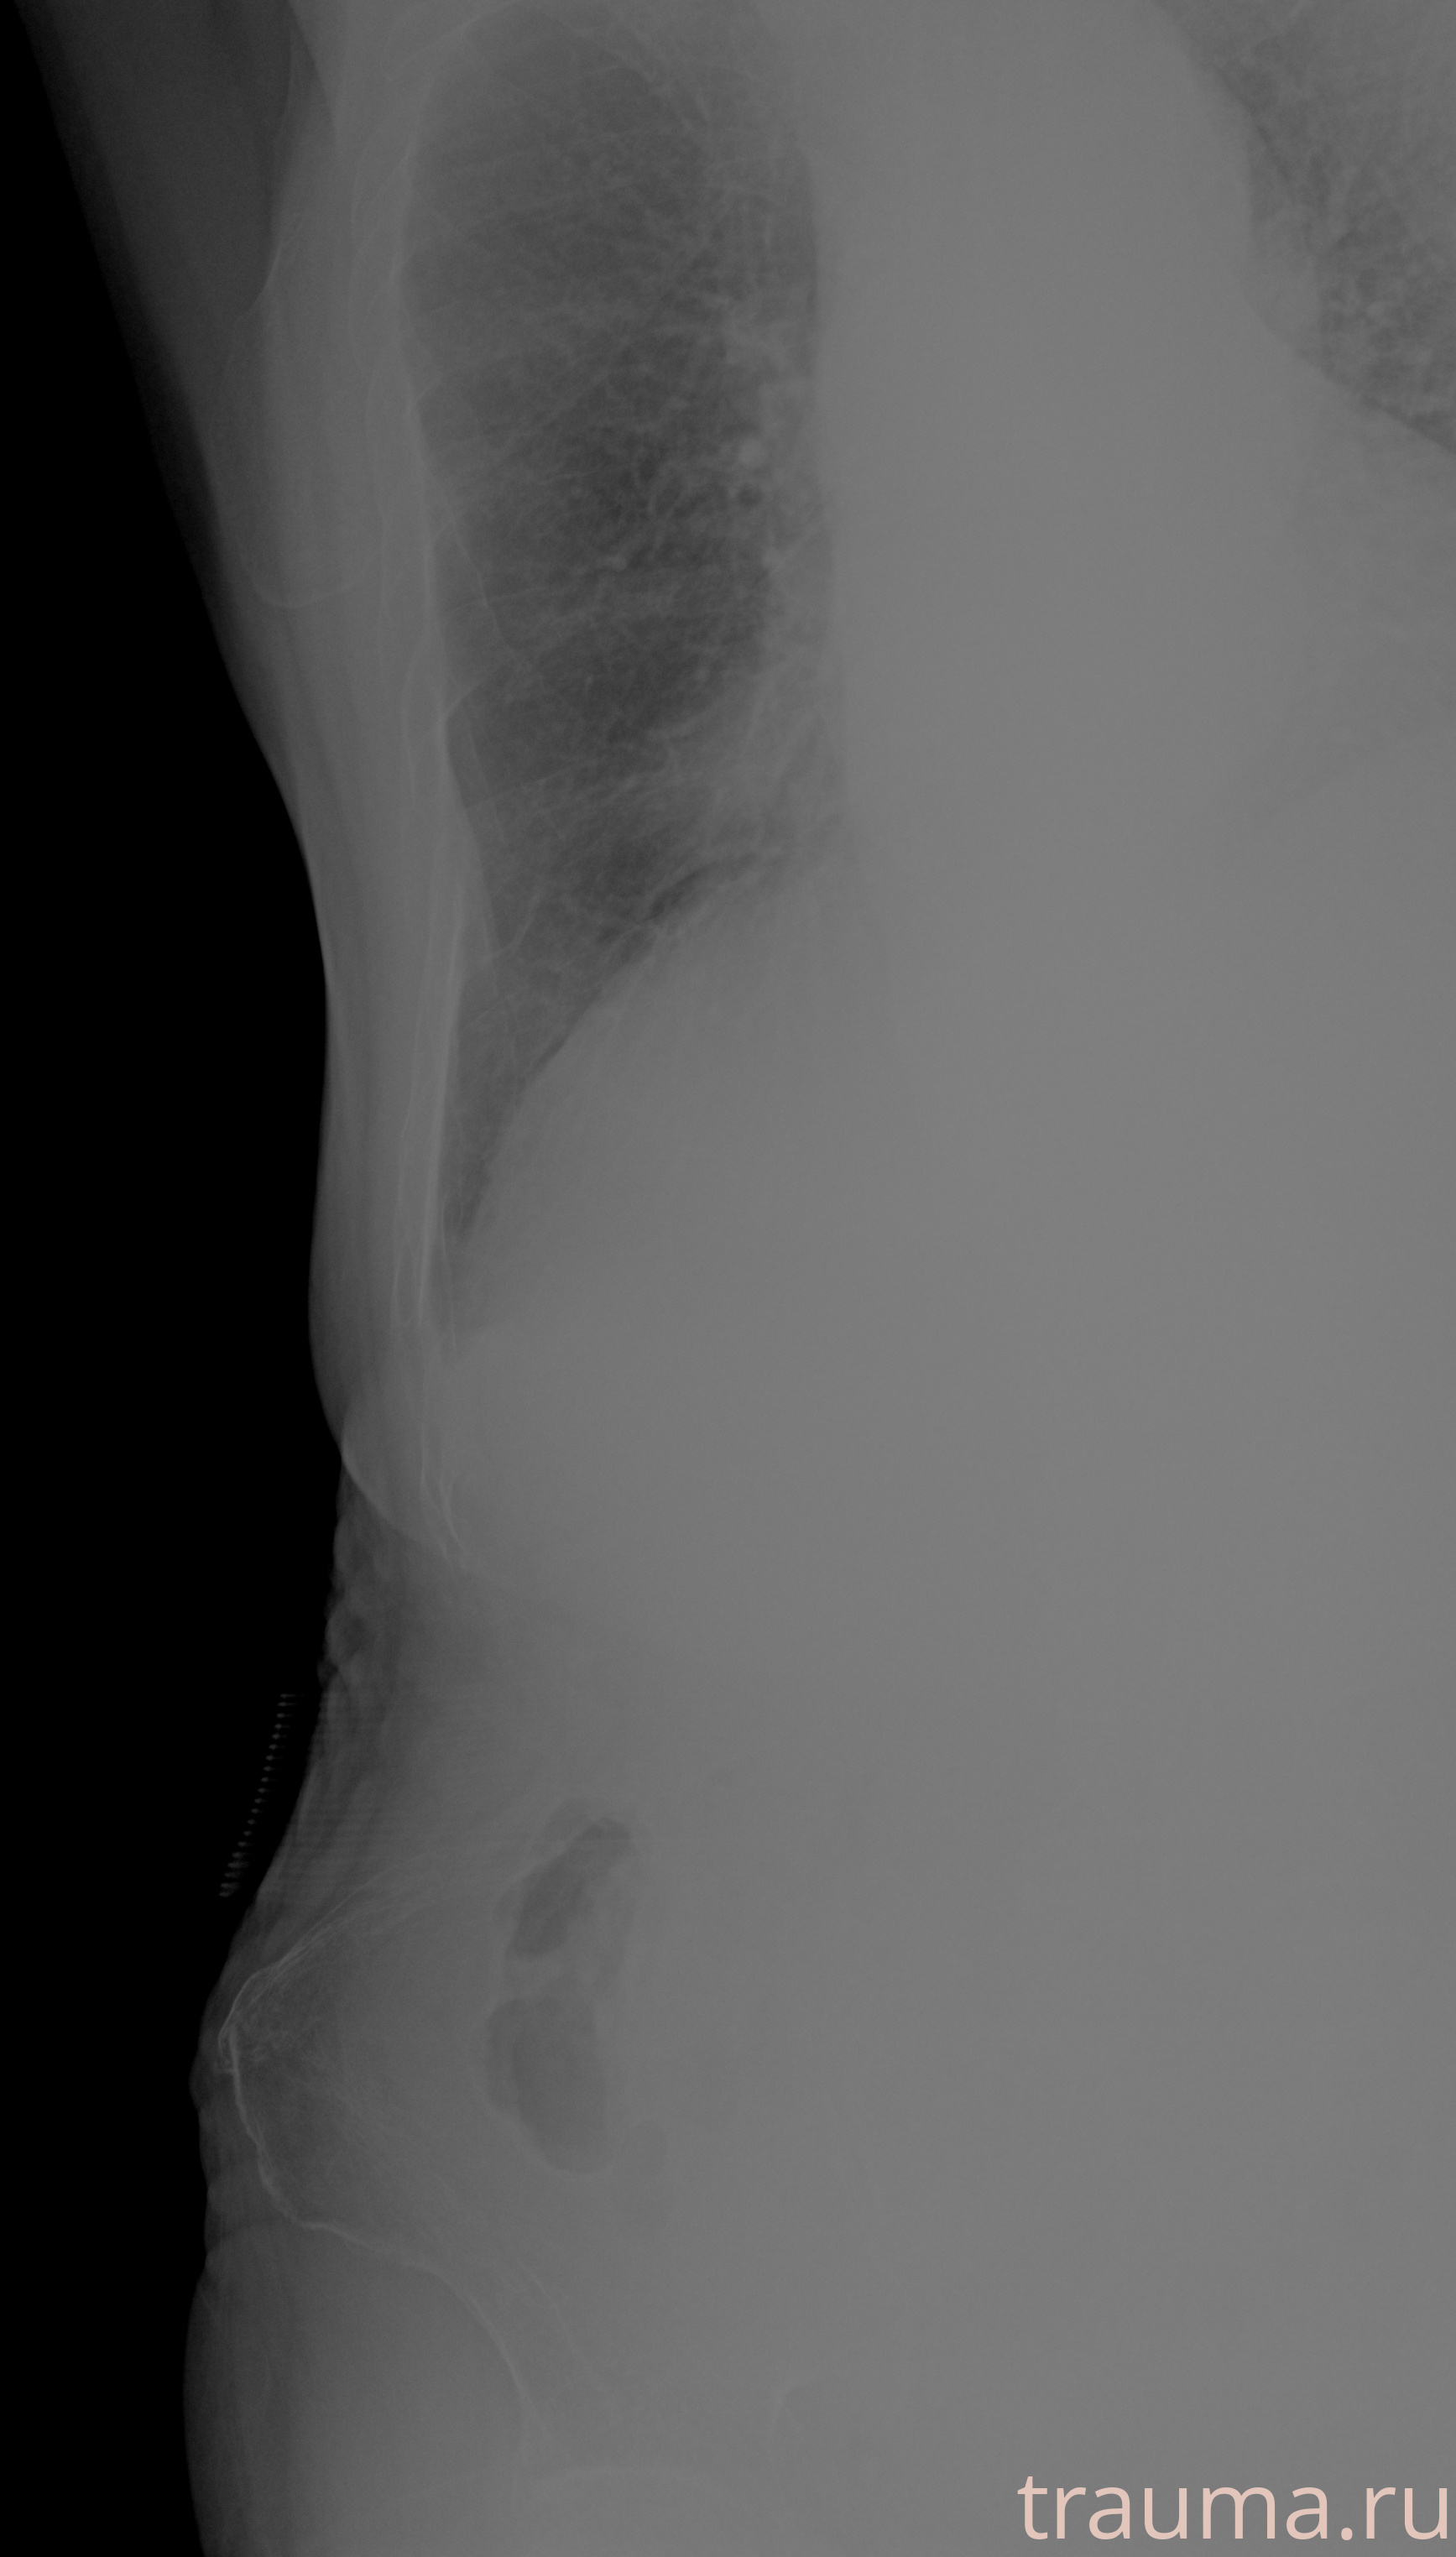

Рентгенограммы

Рентген на дому: по вашему адресу приезжает врач-рентгенолог, травматолог-ортопед с мобильным рентгеновским аппаратом, проводит диагностику травмы или заболевания, делает необходимые рентгенограммы, дает рекомендации по дальнейшему лечению. Получить качественные снимки в домашних условиях возможно благодаря уникальной методике, разработанной МосРентген Центром для института  Склифосовского

при переломе шейки бедра и пневмонии от компании МосРентген Центр - партнера Института имени Склифосовского